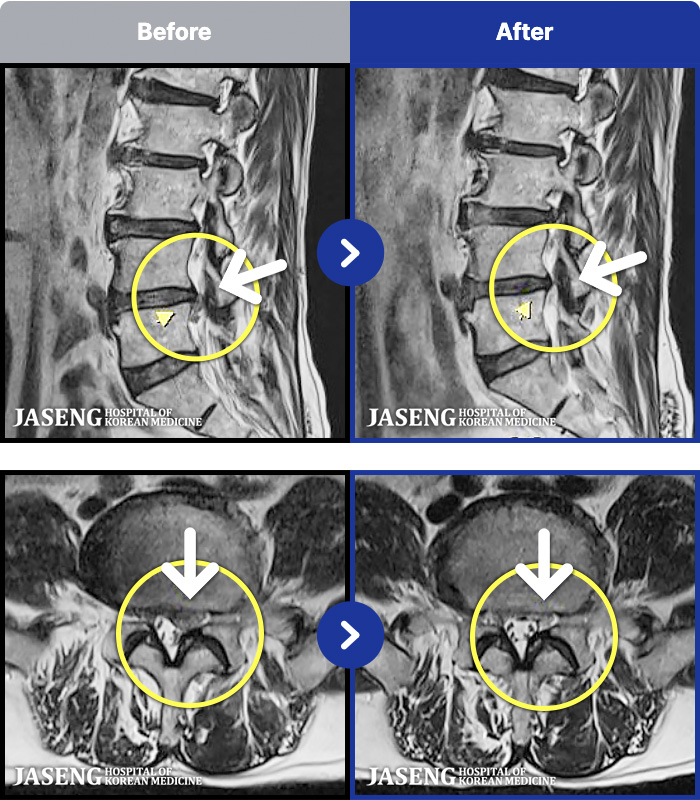

- MRI ġ

MRI ġ

1,237 MRI ũ ʸ Ȯϼ.